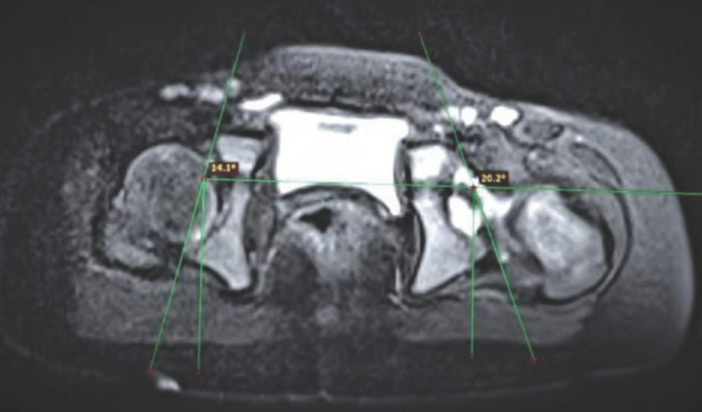

Material and methods: A prospective cohort study was conducted in unilateral idiopathic DDH cases those who underwent an open reduction in the age group of one to four years. Pre- and post-operative MRI was done to assess various acetabular and femoral parameters. Intra-operatively, osteotomy was planned. Based on stability assessment given by Zadeh et al Clinical follow-up assessment was done at three- and six-month post-op. Functional assessment using Modified McKay's criteria was done at six months follow-up.

Results: Out of 15 cases, seven children underwent only open reduction (OR), whereas eight underwent OR with Salter's osteotomy. Based on pre-op acetabular index and anteversion, Salter's osteotomy should be done in 14 out of 15 cases, but intra-operative stability test precluded Salter's in 6 cases. Post-operative anterior sectoral angle and femoral head coverage percentage were better in OR with Salter's group than OR-only group, but not statistically significant. Functional assessment at final follow-up showed all OR with Salter's group cases were Grade I, whereas in OR-only group, 4 were Grade I and 3 were Grade II.